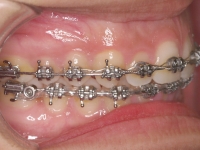

Premolar mandibular incluido + fenestración

45 incluido